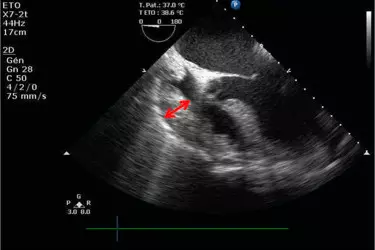

Echo also can pinpoint areas of heart muscle that aren't contracting well because of poor blood flow or injury from a previous heart attack. A type of echo called Doppler ultrasound shows how well blood flows through your heart's chambers and valves. A healthy heart must have an Ejection Fraction of 60% which means that each time your heart contracts it pumps 60% of the blood from the Left Ventricle to the Aorta. If the ejection fraction is low it means that heart will have to work more to pump the same amount of blood and this may slowly lead to heart failure. So getting an echocardiography regularly is a cheap and effective way of finding about the health of your heart.

Echoccardiography can detect many heart problems. Some might be minor and pose no risk to you. Others can be signs of serious heart disease or other heart conditions. An echocardiogram is key in determining the health of the heart muscle, especially after a heart attack. It can also reveal heart defects in unborn babies. If you’re diagnosed with a heart condition, your doctor will work with you to develop a treatment plan that works best for you. The cost of 2d Echo test is Rs. 3500 while the cost of Stress Echo test is Rs. 5500. The cost of Dobutamine Stress Echo Test is Rs. 6000.